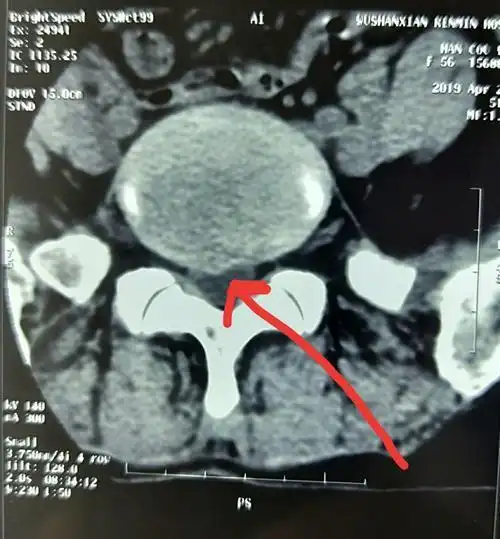

椎间盘膨出 黄色箭头:椎间盘突出 红色箭头:椎间盘脱出 腰椎间盘突出